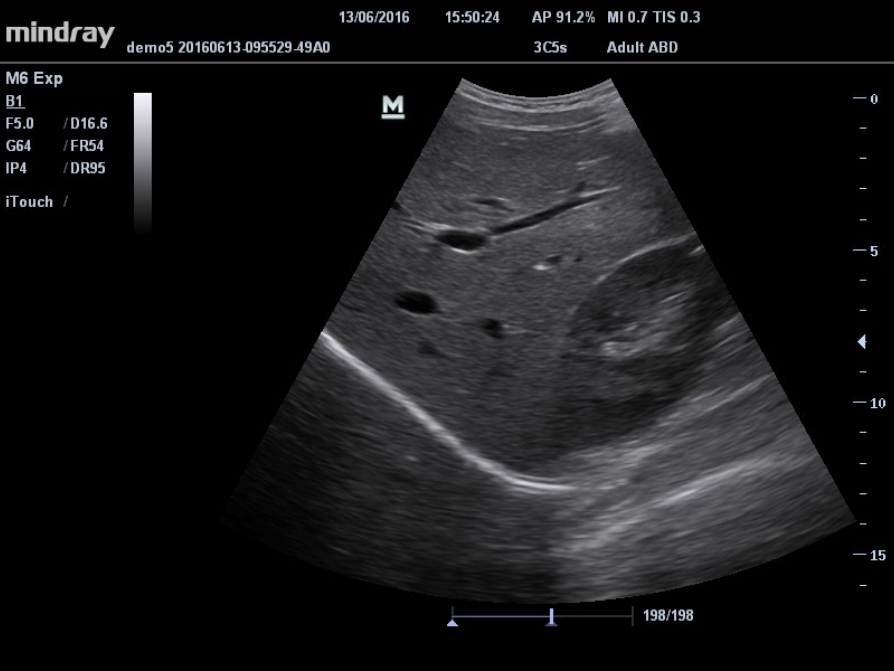

Gain improved image quality based on auto structure detection.

- Sharper & Continuous Edges

- Smooth Uniform Tissues

- Cleaner ŌĆśno echo areasŌĆÖ

iTouch? (Auto Image Optimization)

Gain instant auto image optimization in B, Color and PW Modes on the click of single key.